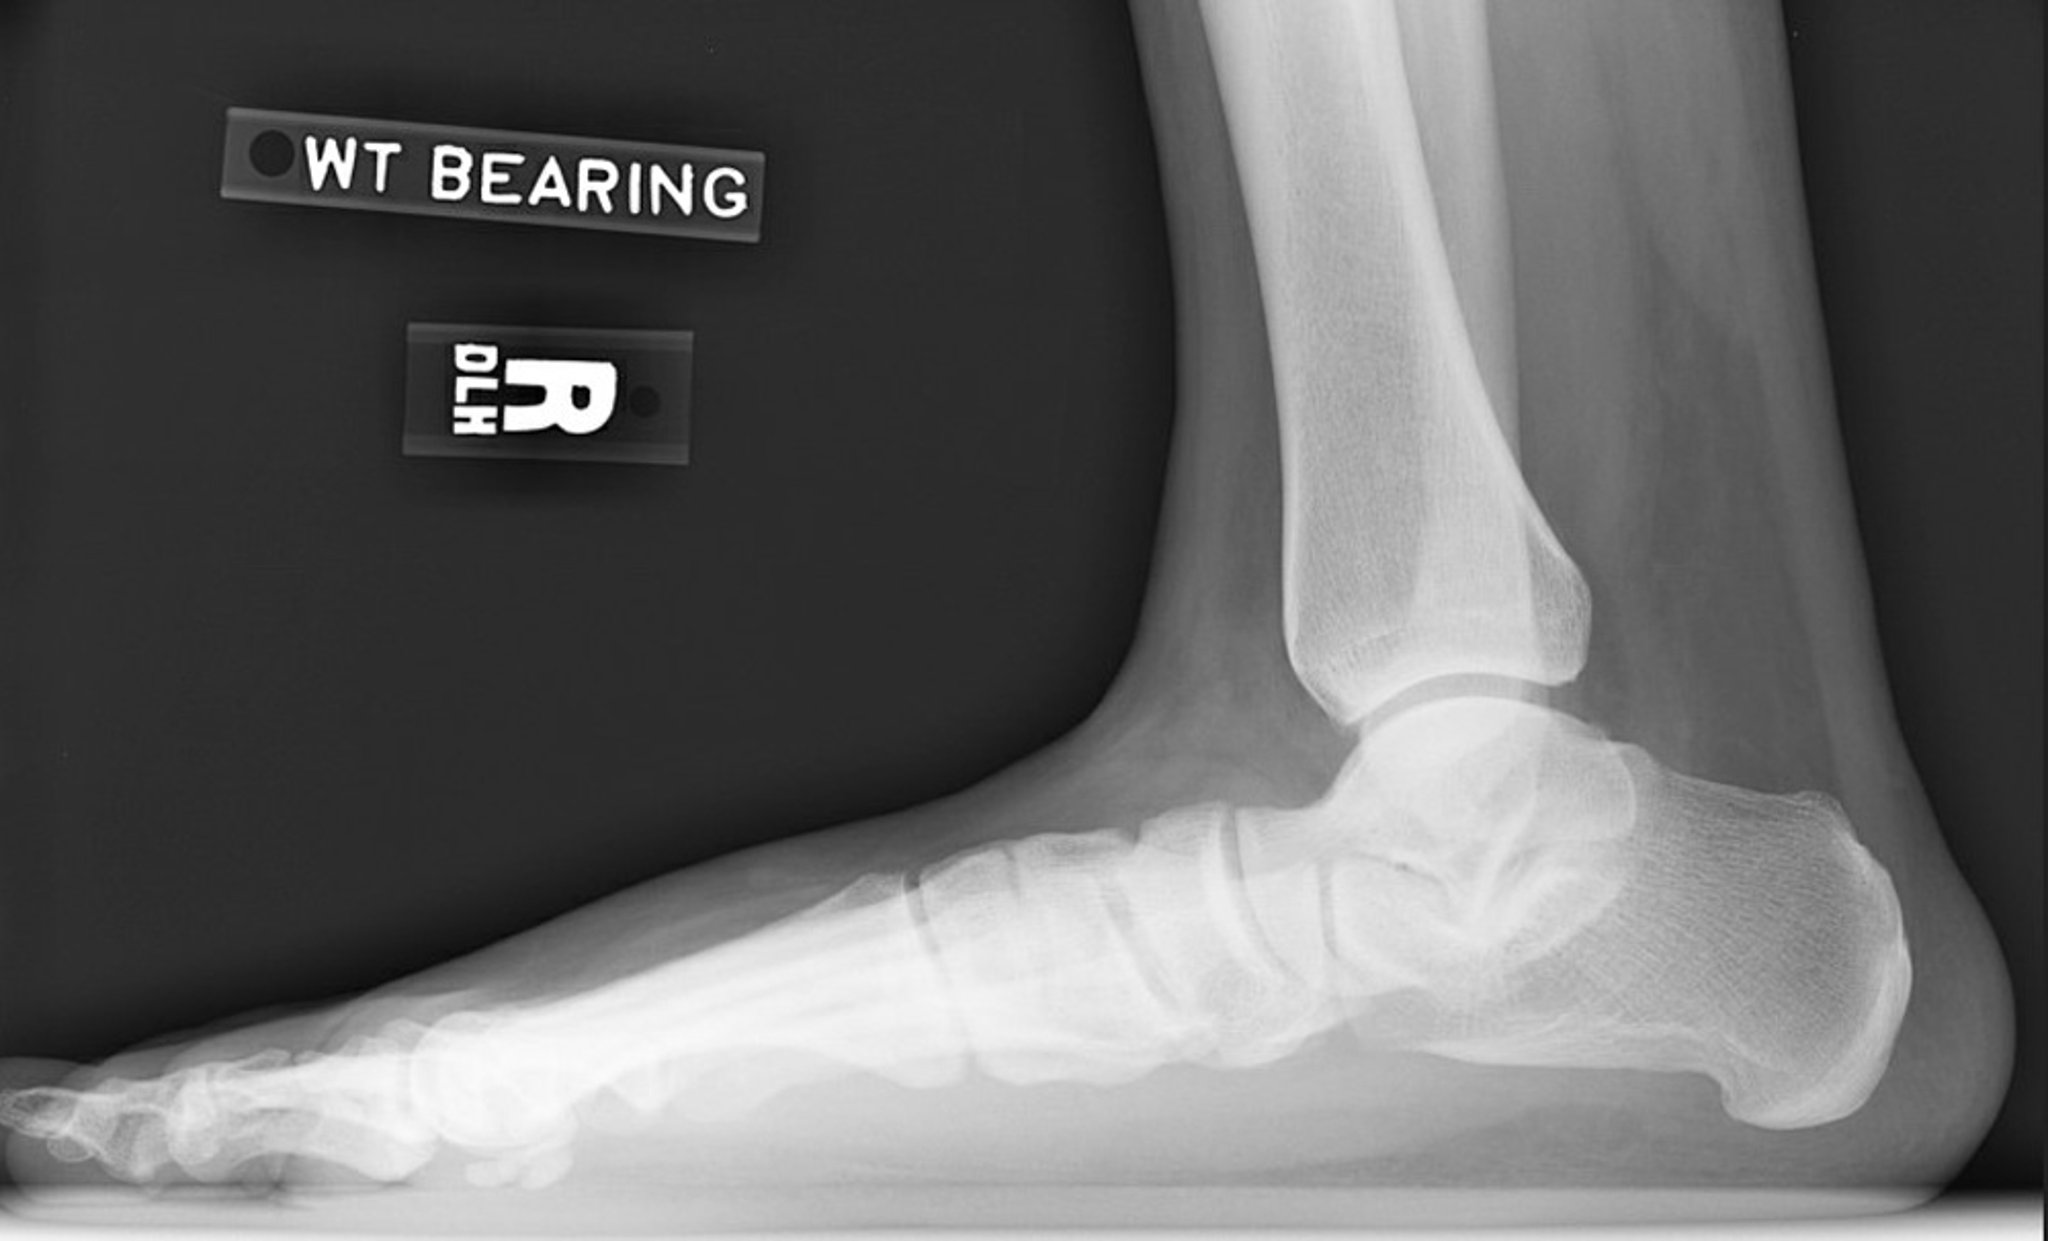

Radiografia do pé chato

Radiografia em perfil do pé direito mostrando uma perda na altura do arco. Observe a diminuição do ângulo de inclinação do calcâneo e do ângulo de declinação do tálus. A articulação subtalar está estreitada, mas a articulação do tornozelo está relativamente preservada.

Imagem cedida por cortesia de James C. Connors, DPM.